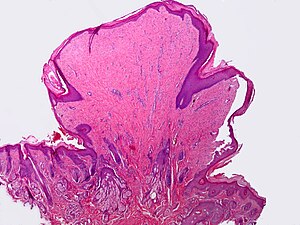

Fibroepithelial polyp. H&E stain. | |

Features:

- On a stalk / epithelium on three sides.

- Benign epidermis.

- Fibrous core.

- +/-Inflammation.